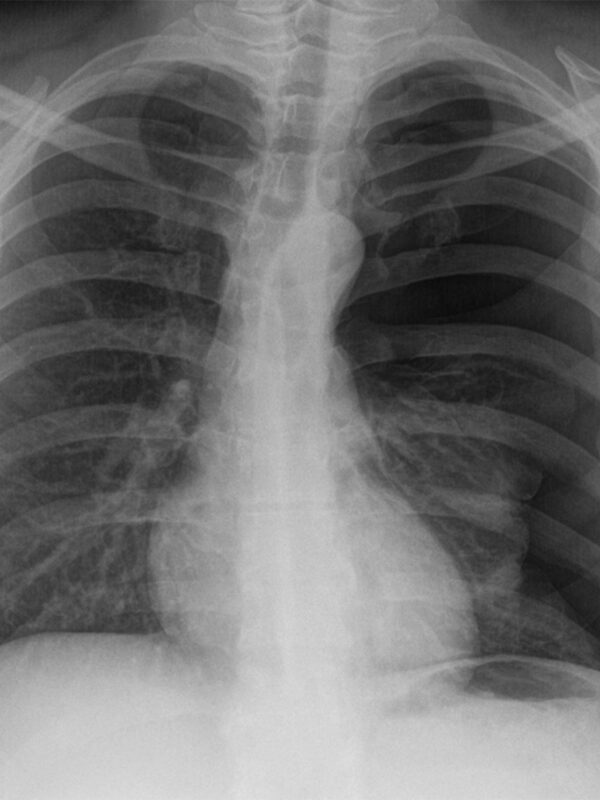

Il collasso del polmone

Il pneumotorace è esattamente questo: il collasso del polmone dovuto ad una pressione negativa, causata da un danno alla membrana sierosa. Vittorio Gemellaro, medico dello sport e direttore sanitario del Fisioradi Medical Center ci aiuta a comprendere in cosa consiste il pneumotorace.

«I polmoni – spiega – sono avvolti da questa membrana, se essa viene bucata si ha un collasso del polmone stesso. E’ come se con un ago si bucasse un palloncino. Il pneumotorace può avvenire in due modi: spontaneamente e in maniera traumatica. Nel primo caso si ha una predisposizione genetica del soggetto, si formano delle bolle d’aria e se si rompono avviene il collasso. Il secondo caso è quello che ci interessa di più perché riguarda traumi sportivi, come la frattura dello sterno, di una costola o della clavicola».

Il bucherellino che avviene nel polmone ne causa il collasso e porta a respirare in maniera preoccupante. Tanto che a volte si pensa al peggio.

Nel caso medio no. La prima cosa da fare è l’ospedalizzazione, dove si fa un drenaggio e il polmone si ristabilisce. Un caso clinico normale prevede tra i sette e i dieci giorni di prognosi, chiaramente ci sono da valutare i danni collaterali.